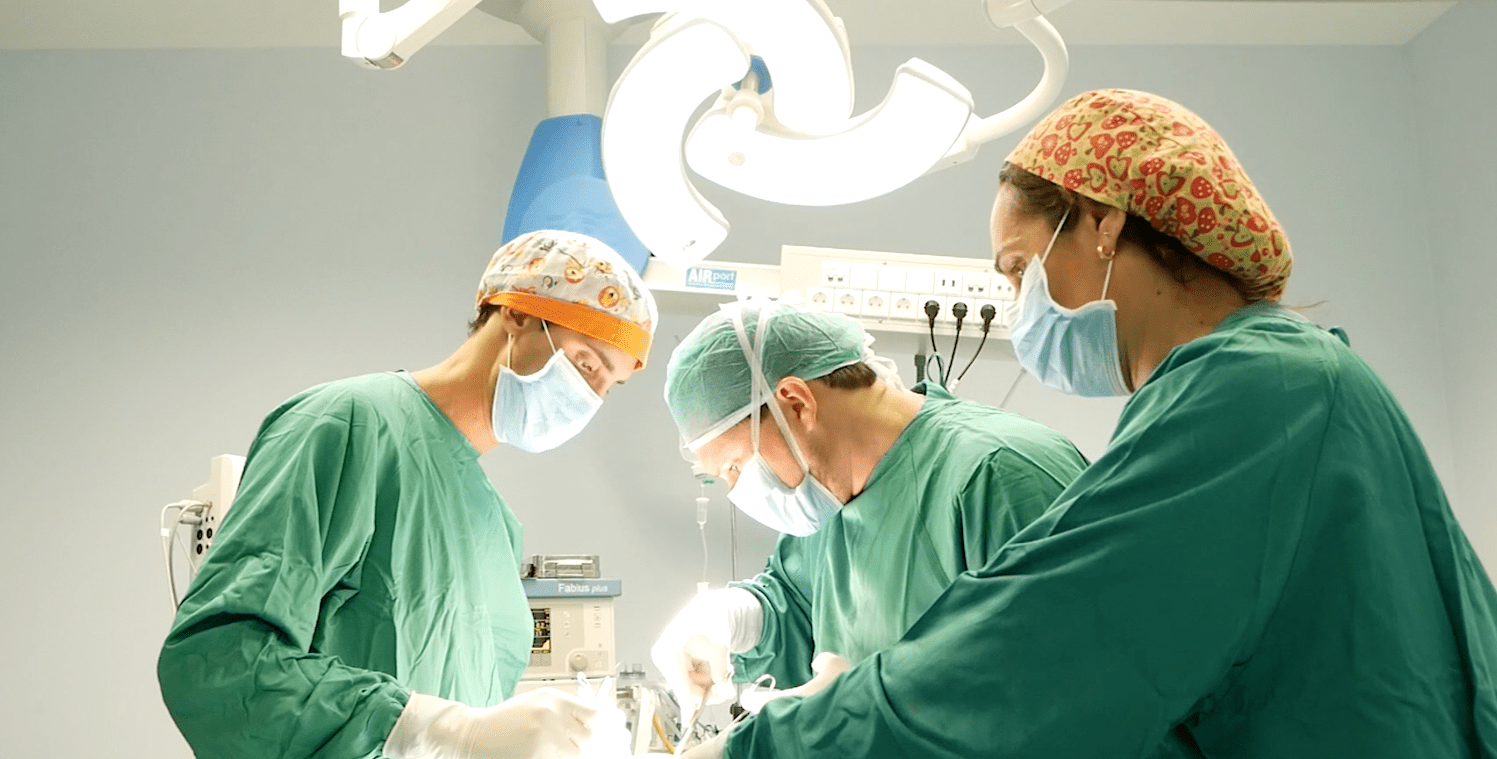

¿Por qué elegir una clínica especializada en alta complejidad reproductiva?

La búsqueda de un embarazo puede llegar a ser un proyecto largo y lleno de incertidumbre, sobre todo cuando el resultado no llega en el momento esperado. Muchas mujeres y […]